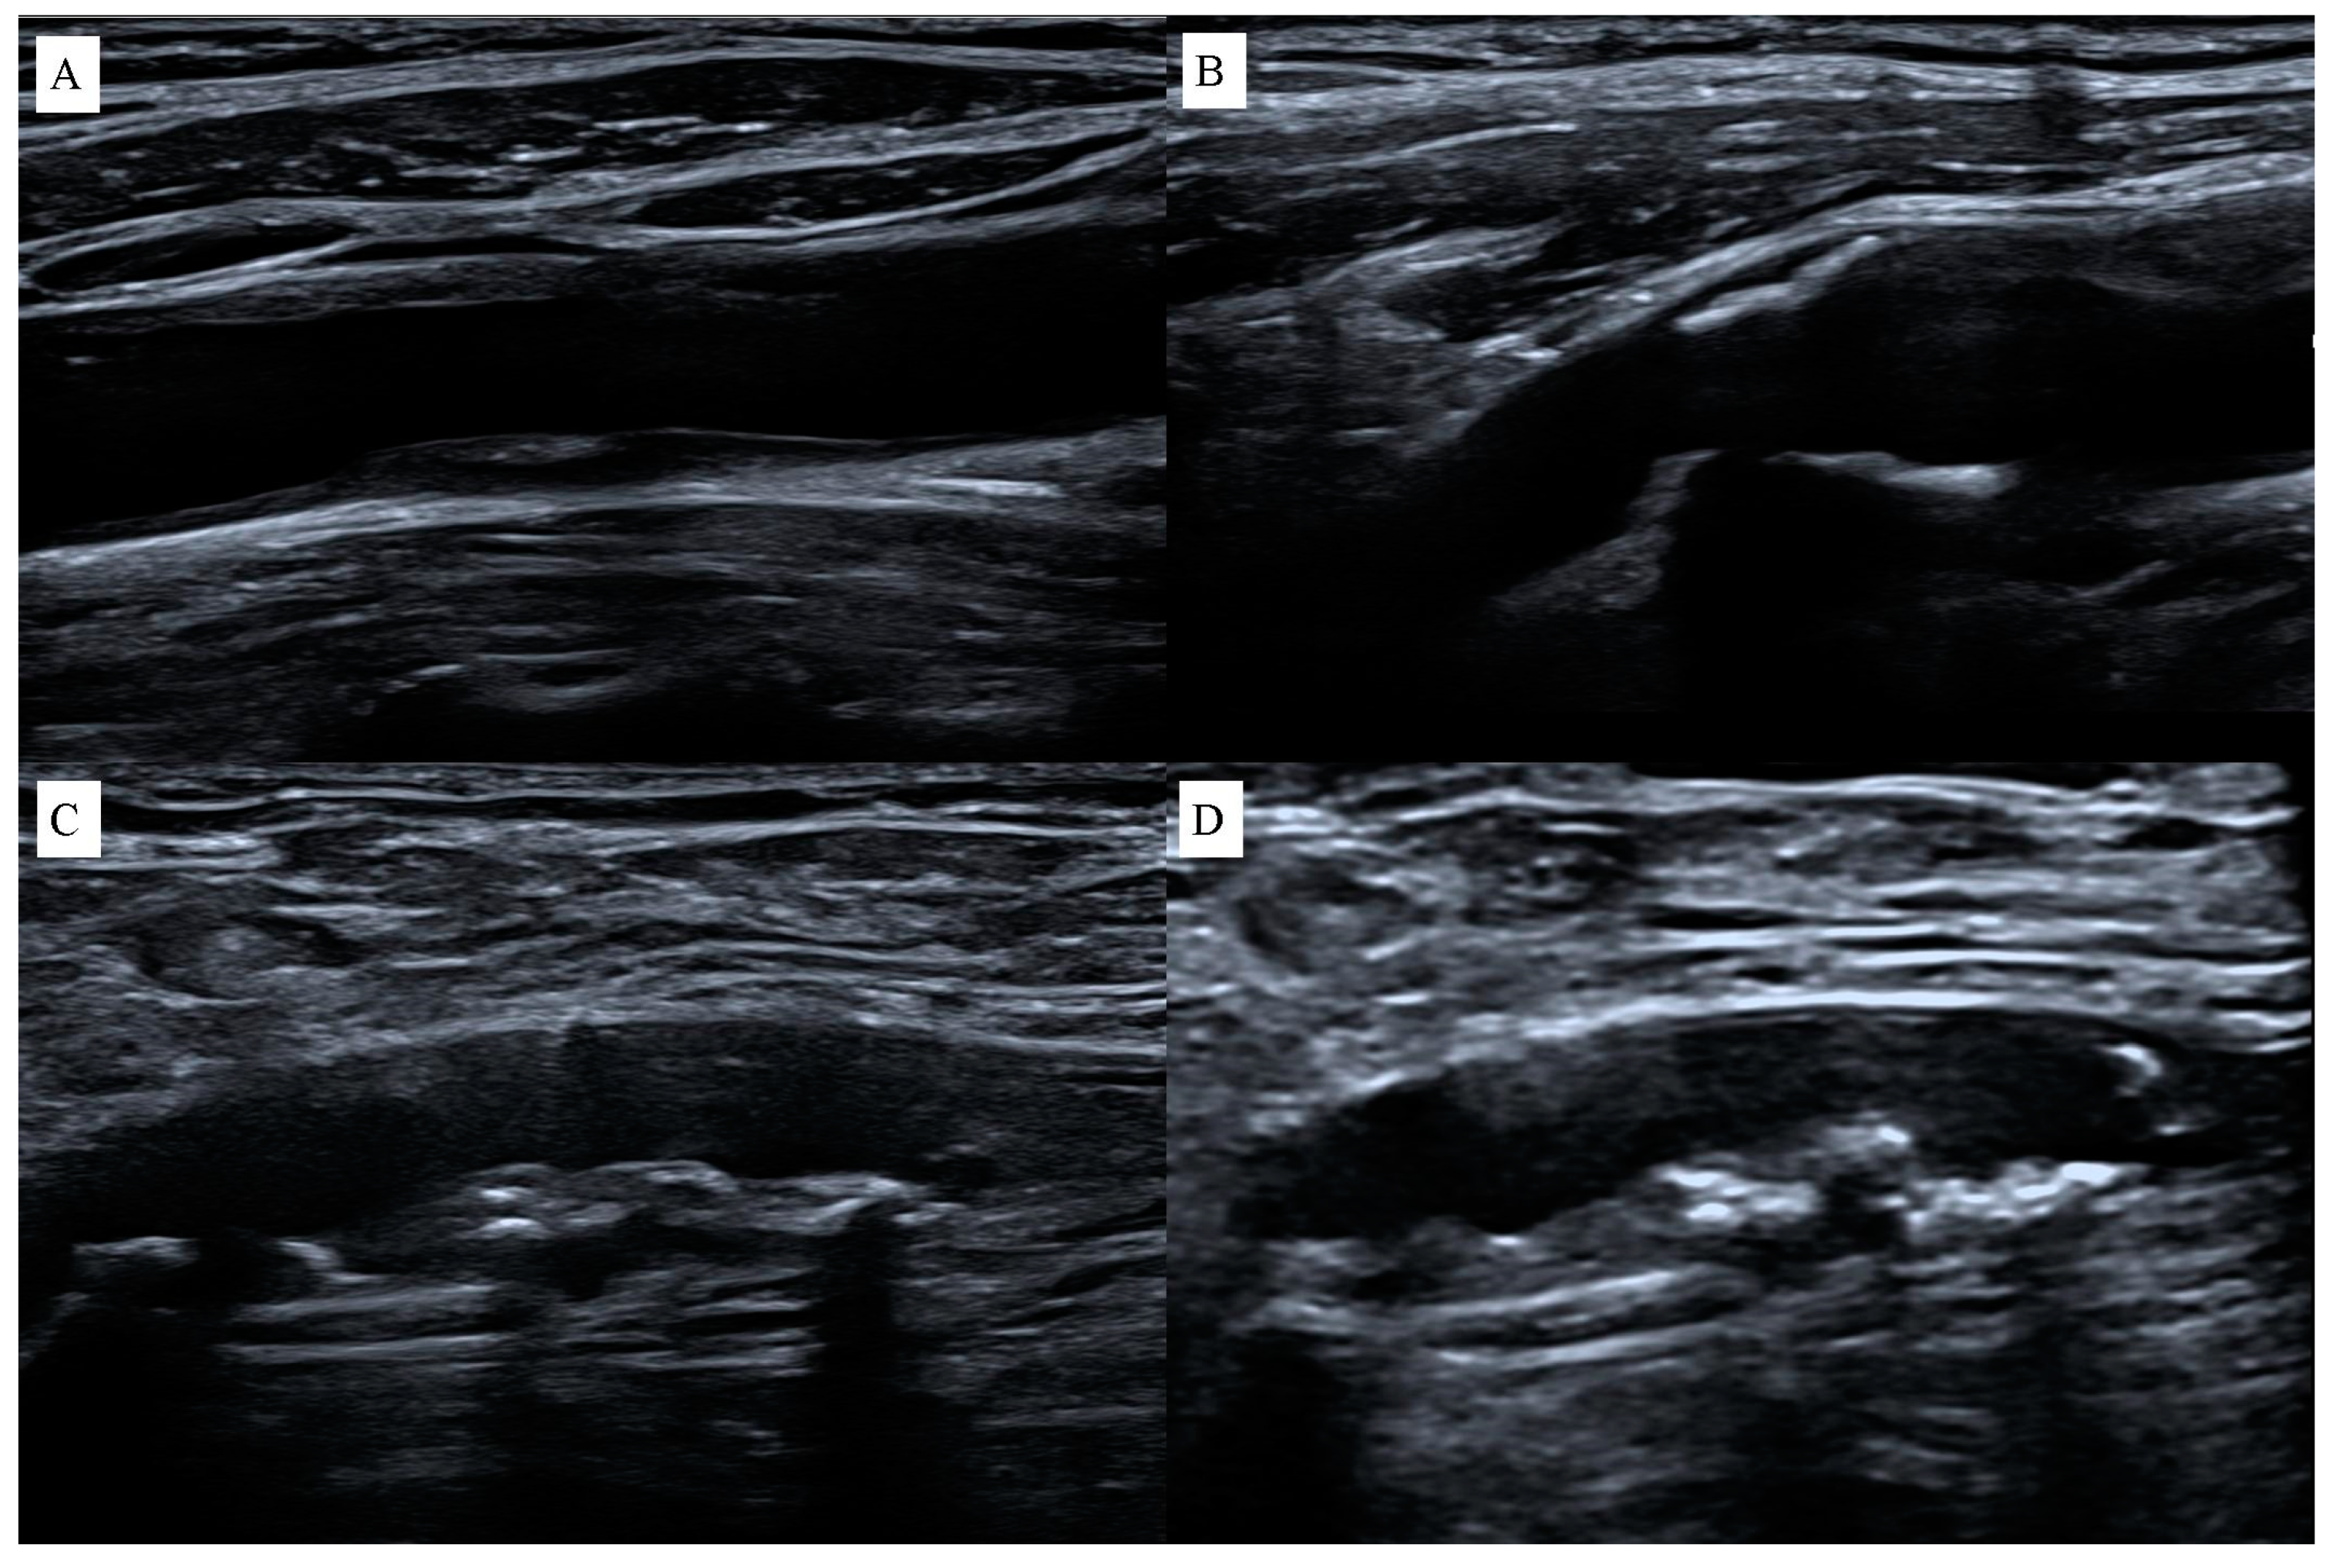

2.1. Ultrasound Imaging Techniques

2.2. The Use of Contrast in USG Imaging of Atherosclerosis